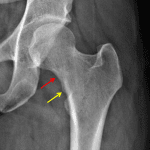

- Focal area of sclerosis in the medial aspect of the left femoral neck with cortical irregularity along the inferior aspect

- Femoral neck stress fracture

Focal area of sclerosis in the medial aspect of the left femoral neck with cortical irregularity along the inferior aspect. These findings raise concern for incomplete femoral neck stress fracture. Consider cross-sectional imaging or bone scan for further evaluation.

Right os acetabuli and bilateral coxa profunda, which although possibly incidental can be seen with pincer-type femoro-acetabular impingement.